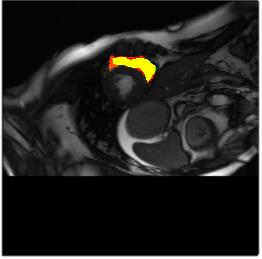

Deep Convolutional Neural Networks (DCNNs) are used extensively in biomedical image segmentation. However, current DCNNs usually use down sampling layers for increasing the receptive field and gaining abstract semantic information. These down sampling layers decrease the spatial dimension of feature maps, which can be detrimental to semantic image segmentation. Atrous convolution is an alternative for the down sampling layer. It increases the receptive field whilst maintains the spatial dimension of feature maps. In this paper, a method for effective atrous rate setting is proposed to achieve the largest and fully-covered receptive field with a minimum number of atrous convolutional layers. Furthermore, different atrous blocks, shortcut connections and normalization methods are explored to select the optimal network structure setting. These lead to a new and full-scale DCNN - Atrous Convolutional Neural Network (ACNN), which incorporates cascaded atrous II-blocks, residual learning and Fine Group Normalization (FGN). Application results of the proposed ACNN to Magnetic Resonance Imaging (MRI) and Computed Tomography (CT) image segmentation demonstrate that the proposed ACNN can achieve comparable segmentation Dice Similarity Coefficients (DSCs) to U-Net, optimized U-Net and hybrid network, but with significantly reduced trainable parameters due to the use of full-scale feature maps and therefore computationally is much more efficient for both the training and inference.